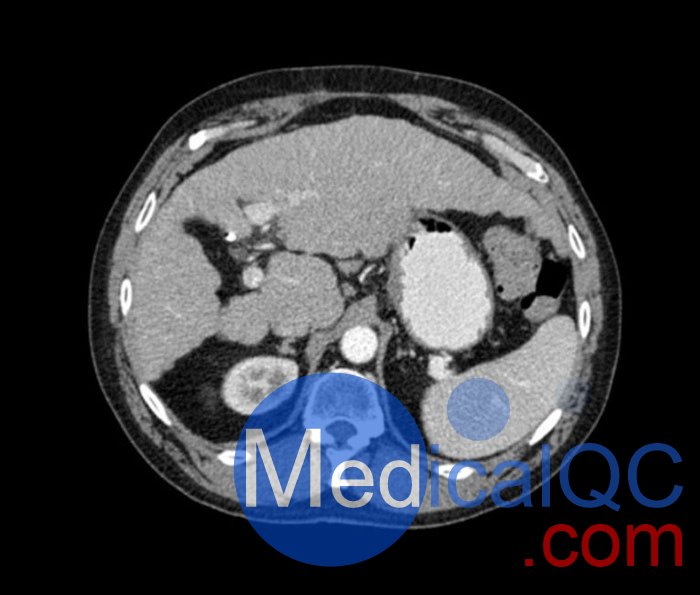

WEK53-04肝硬化腹部模體,WEK53-04腹部模體代表膽囊切除術(shù)后的腹部,帶有小夾子。肝臟有肝硬化的典型體征,在第三腰椎水平植入下腔靜脈過濾器。兩個腎臟都有囊性病變,左側(cè)有一小塊腎結(jié)石。

真實模擬脈管系統(tǒng)、骨骼和軟組織,包括肝臟、胰腺、脾臟、腎上腺、腎臟、胃、小腸和結(jié)腸。

• 肝硬化

• 膽囊切除術(shù)

• 下腔靜脈濾器

• 腎囊腫

• 腎結(jié)石

• 淋巴結(jié)腫大